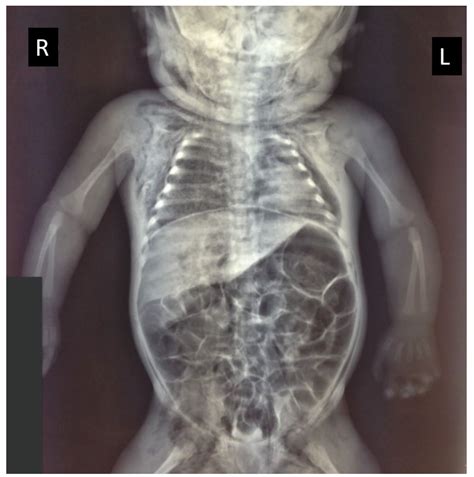

Diagnosing Congenital Pulmonary Airway Malformations (Cpam) typically involves a combination of prenatal and postnatal evaluations. Prenatal diagnosis is often made through ultrasound or magnetic resonance imaging (MRI), which can detect abnormalities in the fetal lungs. Postnatal diagnosis may involve chest X-rays, computed tomography (CT) scans, or MRI to confirm the presence and type of Cpam.

Early diagnosis is crucial for managing Cpam, as it allows healthcare providers to plan appropriate interventions and monitor the condition closely. In some cases, prenatal interventions may be necessary to improve outcomes for the fetus.

• Respiratory Distress: Infants with Cpam may experience respiratory distress, which can be life-threatening if not managed promptly.